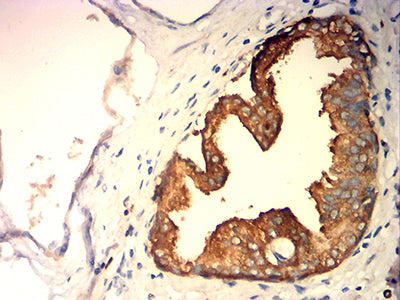

分类: 科研抗体货号: 32257别名: hK2; hGK-1; KLK2A2应用: IHC,FCM反应种属: Human